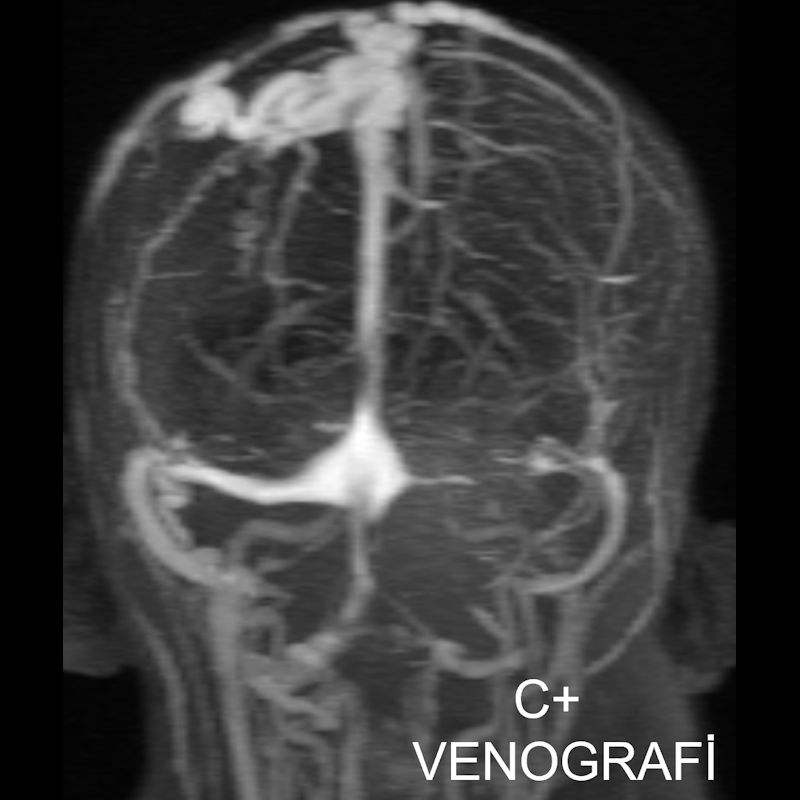

2. B) Kontrastlı MR venografide orta hatta cilt altı dilate (oklar), tortiyoze emisserian vaskuler yapıların superior sagital sinus ile ilişkisi ve devamlılığı (ok) izlenmektedir.